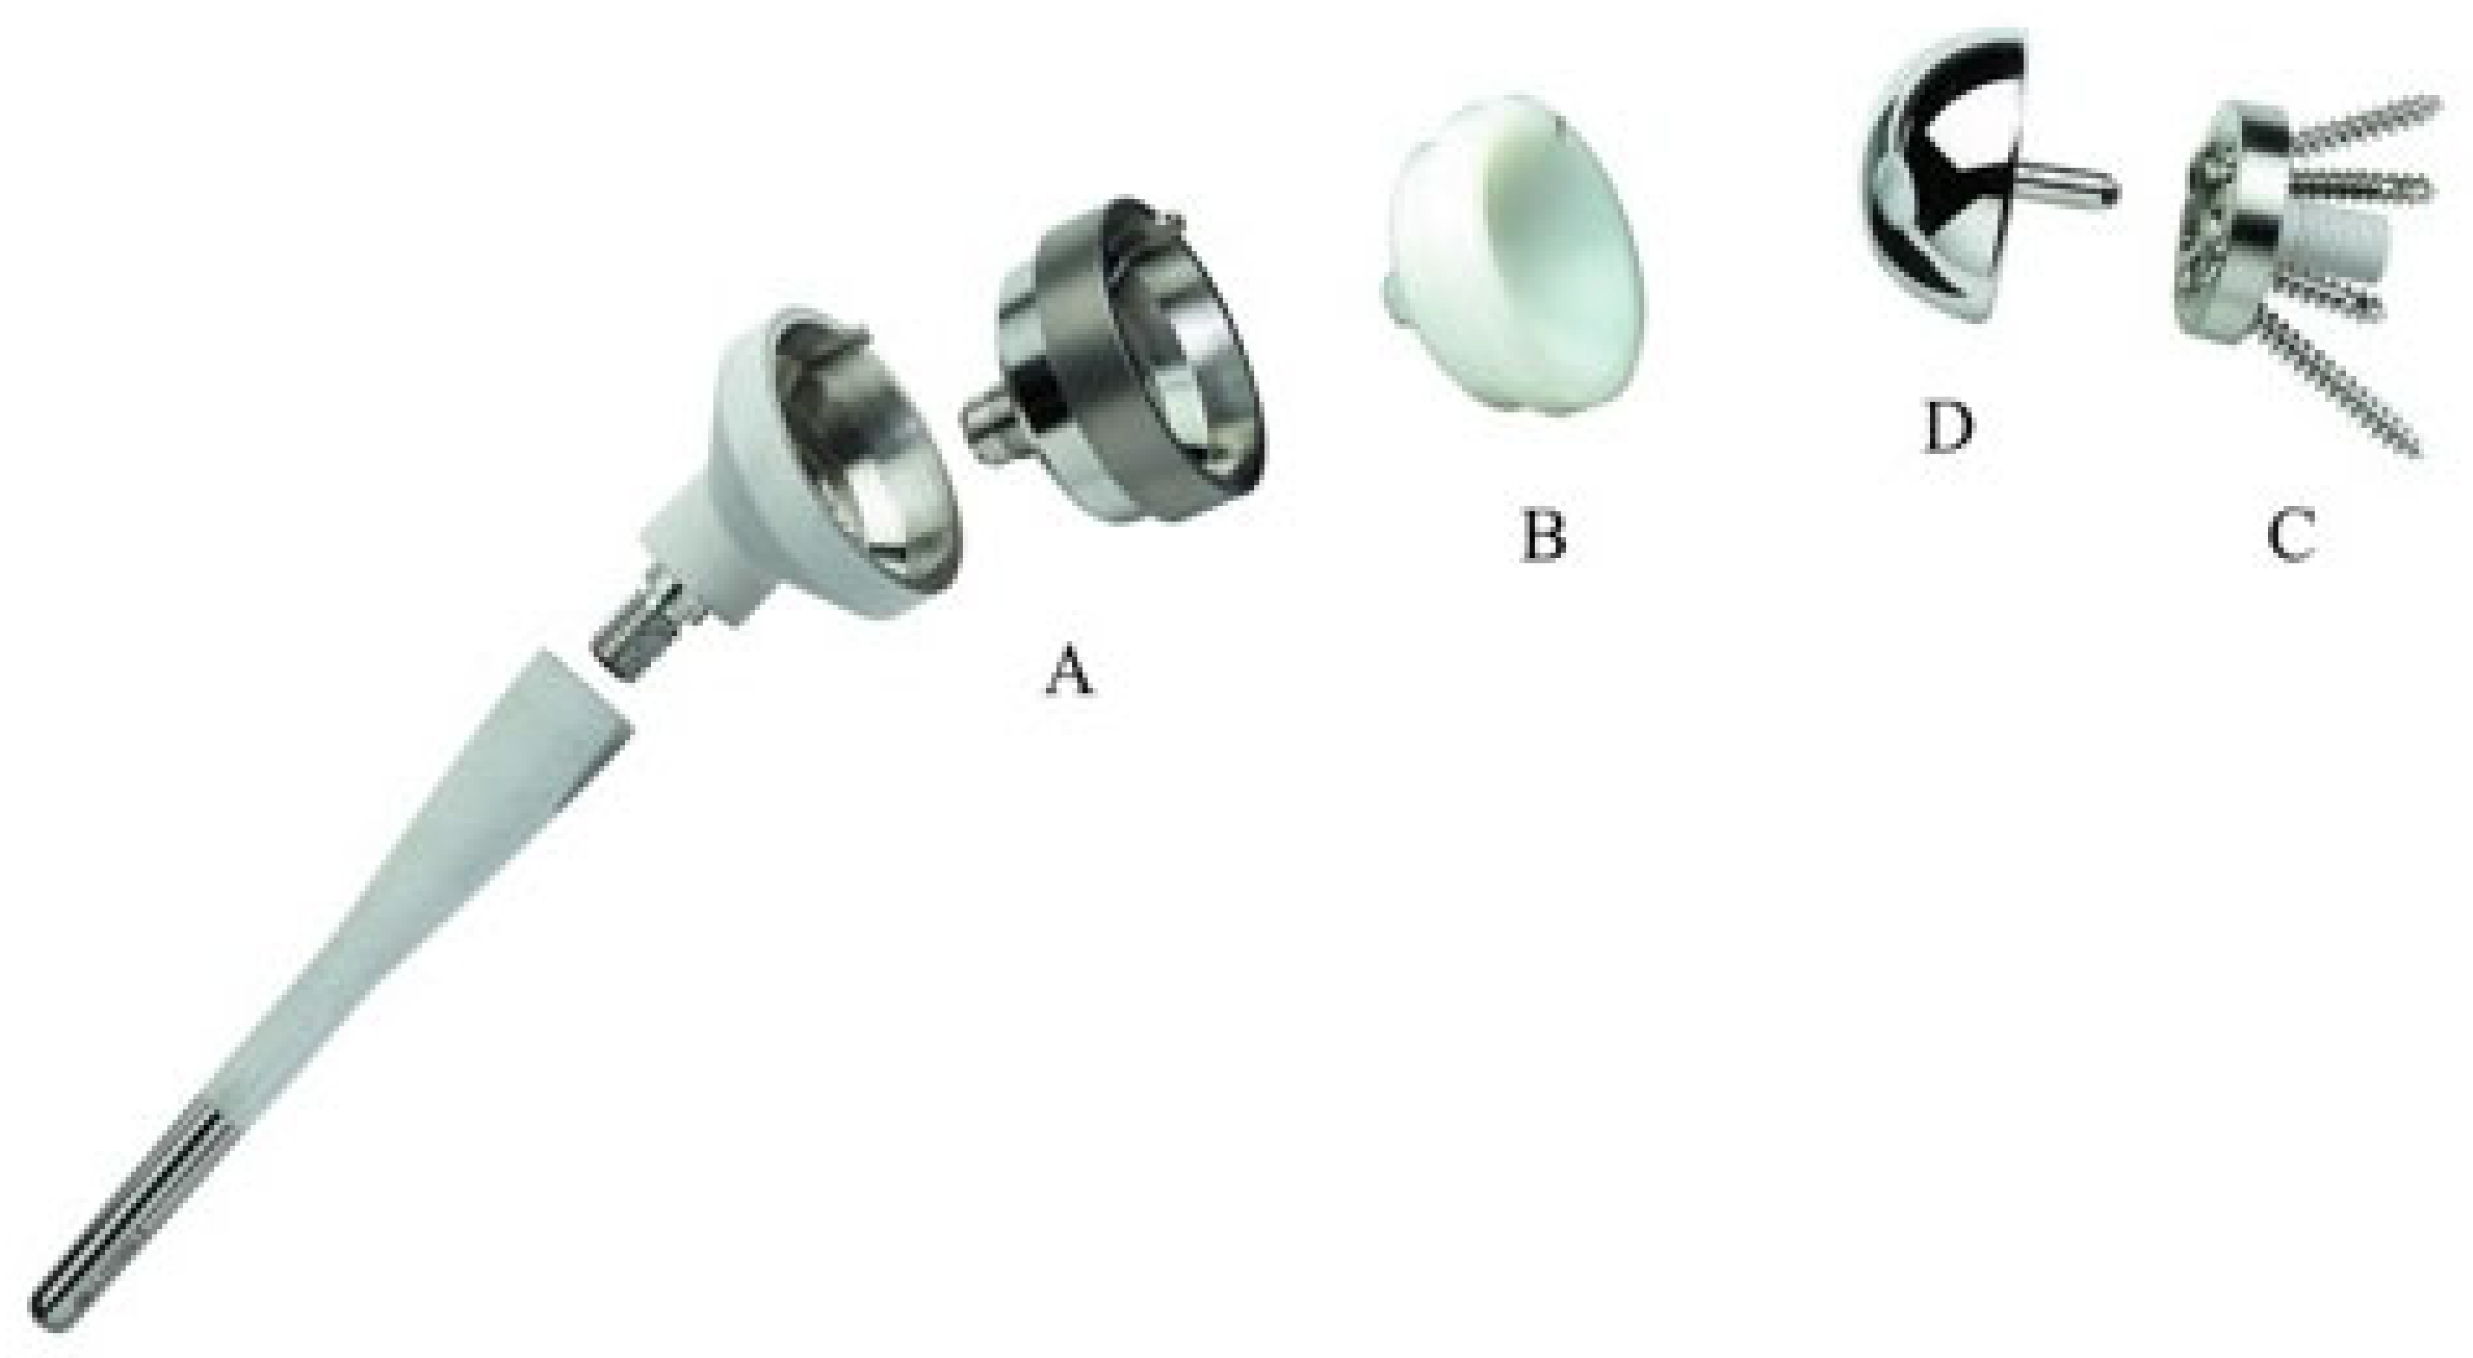

3. Biomechanics of Reverse Shoulder Arthroplasty

- Medialization and inferiorization of the joint CoR, achieved through medialization of the glenoid and the humerus with a 145° neck–shaft angle to increase the deltoid lever arm.

- Setting the CoR at the bone–prosthetic glenoid interface, thus reducing shear forces on the metal back.

- Distalization of the humerus, thus tensioning the deltoid to recover strength even from the onset of the motion.

- Semi-constrained design, obtained with a convex glenosphere and a concave humeral cup with the same curvature radius, creating a ball and socket joint and providing a stable fulcrum and ensuring static stability.

- Boileau, P.; Watkinson, D.J.; Hatzidakis, A.M.; Balg, F. Grammont Reverse Prosthesis: Design, Rationale, and Biomechanics. J. Shoulder Elb. Surg. 2005, 14, S147–S161. [Google Scholar] [CrossRef] [PubMed]

- Routman, H.D.; Flurin, P.-H.; Wright, T.W.; Zuckerman, J.D.; Hamilton, M.A.; Roche, C.P. Reverse Shoulder Arthroplasty Prosthesis Design Classification System. Bull. Hosp. Jt. Dis. 2015, 73 (Suppl. 1), S5–S14. [Google Scholar]